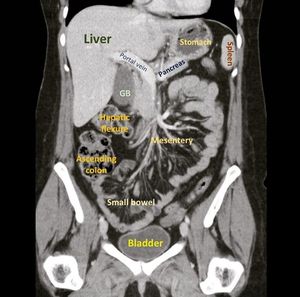

X ray abdomen erect